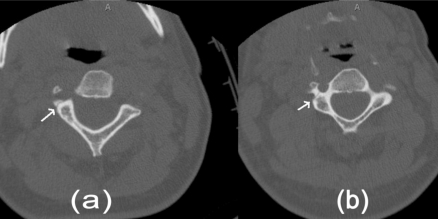

简介:当采用适当的筛查标准时,钝性脑血管损伤(BCVI)在所有钝性创伤中占1-2.7%。相当数量的BCVI患者有潜伏期或无症状期,在此期间,基于适当使用血管造影的治疗干预可能会降低缺血性卒中的风险。方法:病例报告和文献复习。结果:一名42岁的女性从摩托车上摔下来,在急诊室神经系统完好。在非对比计算机断层扫描(CT)上发现累及颈椎横孔的骨折,但未进行BCVI血管造影筛查。随后,她患上了缺血性中风,导致严重残疾。本文回顾了针对BCVI筛查标准的使用及后续治疗的已发表研究。结论:BCVI可导致缺血性脑卒中显著的发病率和死亡率。BCVI与缺血性脑卒中的发生之间往往有一段潜伏期。特定的危险因素可用于确定需要导管或CT血管造影筛查的患者。抗血栓药物治疗是BCVI的主要治疗方法,可以降低缺血性卒中的发生率。钝性创伤患者无症状BCVI的识别和治疗可以预防缺血性脑卒中的主要是年轻人群。

Introduction: Blunt cerebrovascular injury (BCVI) is found in 1-2.7% of all blunt trauma when appropriate screening criteria are employed. A significant number of patients with BCVI have a latent, or asymptomatic period, in which therapeutic intervention based on the appropriate use of angiographic imaging may decrease the risk of an ischemic stroke. Methods: Case report and review of literature. Results: A 42 year old woman suffered a fall off a motorcycle and was neurologically intact in the emergency room. Fractures involving the transverse foramen of cervical vertebrae were found on non-contrast Computed Tomography (CT) but screening for BCVI with angiographic imaging not performed. She subsequently suffered an ischemic stroke resulting in significant disability. Published studies that address the use of screening criteria for BCVI and subsequent management are reviewed. Conclusion: BCVI results in significant morbidity and mortality attributable to ischemic stroke. There is often a latent period between BCVI and occurrence of ischemic stroke. Specific risk factors can be used to identify patients requiring screening with catheter or CT angiography. Treatment with antithrombotic agents is the mainstay of treatment of BCVI and may reduce the rate of ischemic stroke. Identification and treatment of asymptomatic BCVI in blunt trauma patients may prevent ischemic stroke in a predominantly young population.